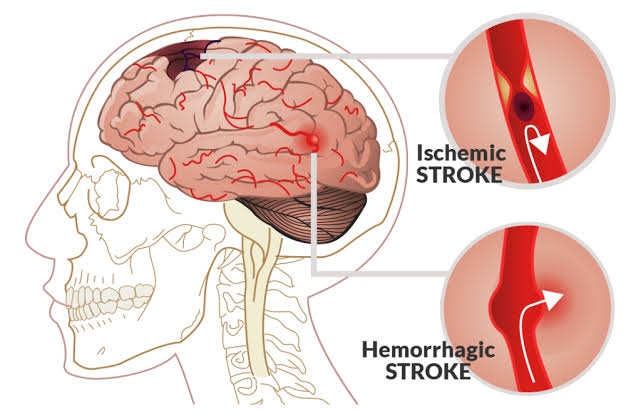

The actual cause of stroke still remains “sudden” loss of blood supply to a part of the brain. Which could be as a result of

1.) obstruction to a blood vessel (Ischemic stroke)

2.) Rupture of a blood vessel (hemorrhagic stroke)